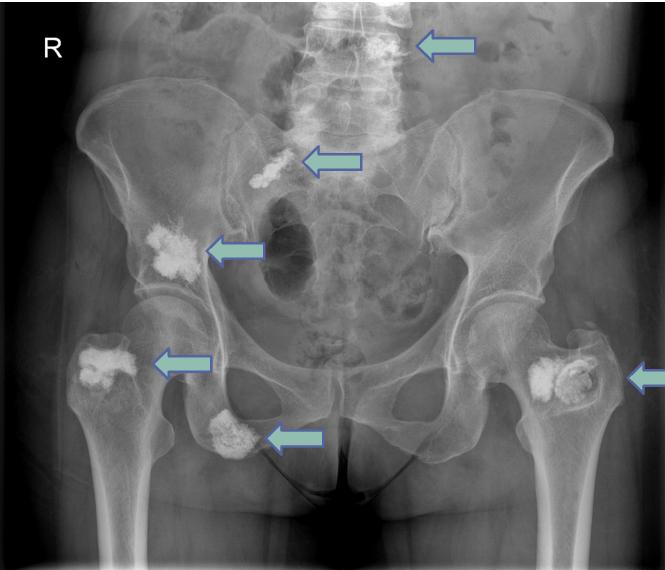

Cementoplasty is a minimally invasive procedure involving the percutaneous injection of bone cement into weakened or tumor-infiltrated bone outside the spine, such as pelvis, acetabulum, femur, or humerus.

Bone metastases causing pain or structural weakness

Osteolytic lesions in weight-bearing bones

- Pain refractory to medical therapy